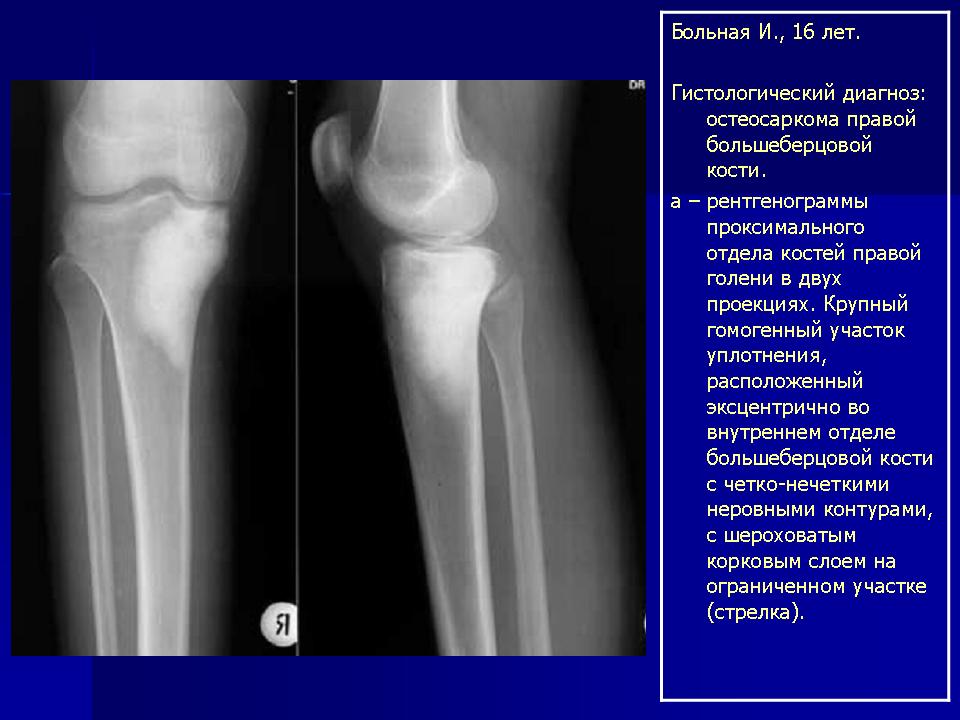

Первым исследованием, на основании которого обычно ставится диагноз остеогенной саркомы, является рентгенодиагностика. Это исследование позволяет заподозрить наличие остеосаркомы у пациента, а также выявляет наличие мягкотканного компонента, патологического перелома, определяет размеры опухоли, и оптимальный уровень проведения биопсии.